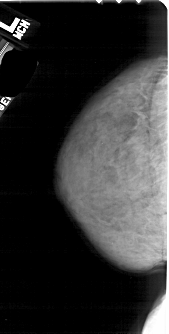

A_1832_1.LEFT_MLO

LEFT_MLO LINES 5491 PIXELS_PER_LINE 2581 BITS_PER_PIXEL 12 RESOLUTION 43.5 NON_OVERLAY

RIGHT_MLO LINES 5371 PIXELS_PER_LINE 2461 BITS_PER_PIXEL 12 RESOLUTION 43.5 OVERLAY

FILE: A_1832_1.RIGHT_MLO.OVERLAY

TOTAL_ABNORMALITIES 1

ABNORMALITY 1

LESION_TYPE CALCIFICATION TYPE PLEOMORPHIC DISTRIBUTION CLUSTERED

ASSESSMENT 3

SUBTLETY 1

PATHOLOGY BENIGN